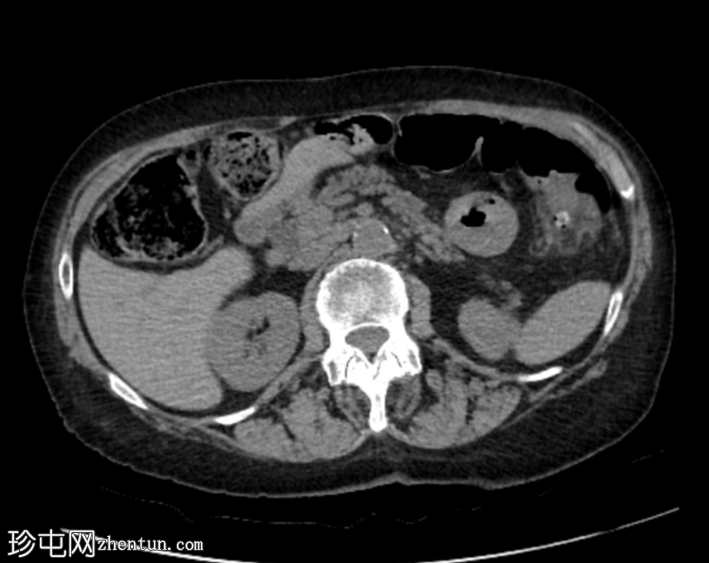

CT

1.png

轴位

平扫

平扫图像显示左侧结肠脾曲处可见小憩室,伴结肠周围脂肪间隙条索状改变,提示急性结肠憩室炎。